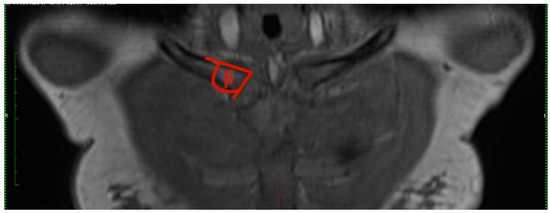

- Clavicular–sternal angle: The lengthwise axis of the clavicle is determined by a line, which is drawn from the middle of the lateral clavicle to the middle of the medial clavicle. The vertical axis of the sternum is drawn from the middle of the cranial end of the sternum to the xiphoid process of the sternum. Those two axes created the obtuse angle gamma (Figure 3).